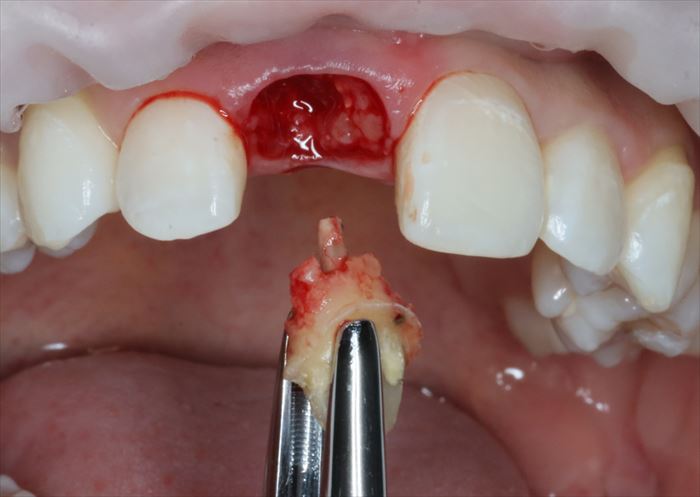

残っていた歯根を抜歯し、顕微鏡下で抜歯窩内部の掻爬を終えました。

心配していた唇側の骨は無事に保存できました。

このように満身創痍な状態で今日までよく頑張ってくれました。